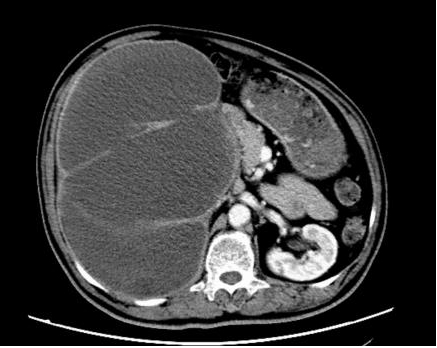

入院后,科室为患者完善影像学、内镜及病理等一系列检查,明确诊断其右肾盂、右输尿管及膀胱均存在恶性肿瘤病灶,其中右输尿管肿瘤引发梗阻,导致右肾严重积水,肾脏体积达650px×500px×175px,病情复杂程度远超常规病例,常规治疗方案难以达到理想疗效。

2026年1月底,患者完成新辅助治疗后,经评估手术条件已成熟,且患者及家属手术意愿明确。在麻醉科、手术室护理团队的全力配合下,李化升主任带领手术团队开始手术。为建立有效操作空间,团队先为患者穿刺抽出3600ml血性尿液,使肿大的肾脏体积有所缩小,随后开展腹腔镜下右肾切除操作。术中发现肾脏与十二指肠等周围组织严重粘连,腔镜下仅能游离约85%,团队随即调整方案,通过开放手术游离剩余部分并顺利取出肾脏。